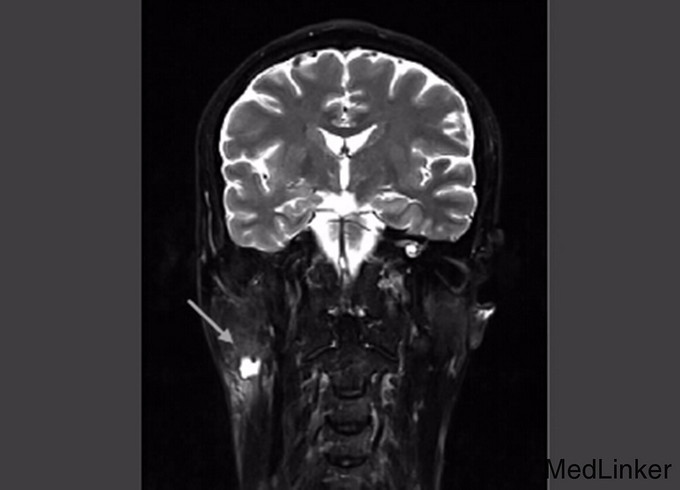

查体:右面颊腮腺区可扪及质地中等约4cm*2cm大小肿块,,界线不清,与周围组织粘连,压痛,以耳根部显著,颌下淋巴结未触及肿大,其它检查正常 辅查:超声检查:右侧腮腺内可见一个不规则低回声包块,大小约43mm*26mm*15m,边界不清,形态不规则,其内可见少许液性暗区;包块内实性部分可探及少许血流信号;MRI平扫与动态增强示:右侧腮腺区占位性病变,含囊性成分,血供欠丰富